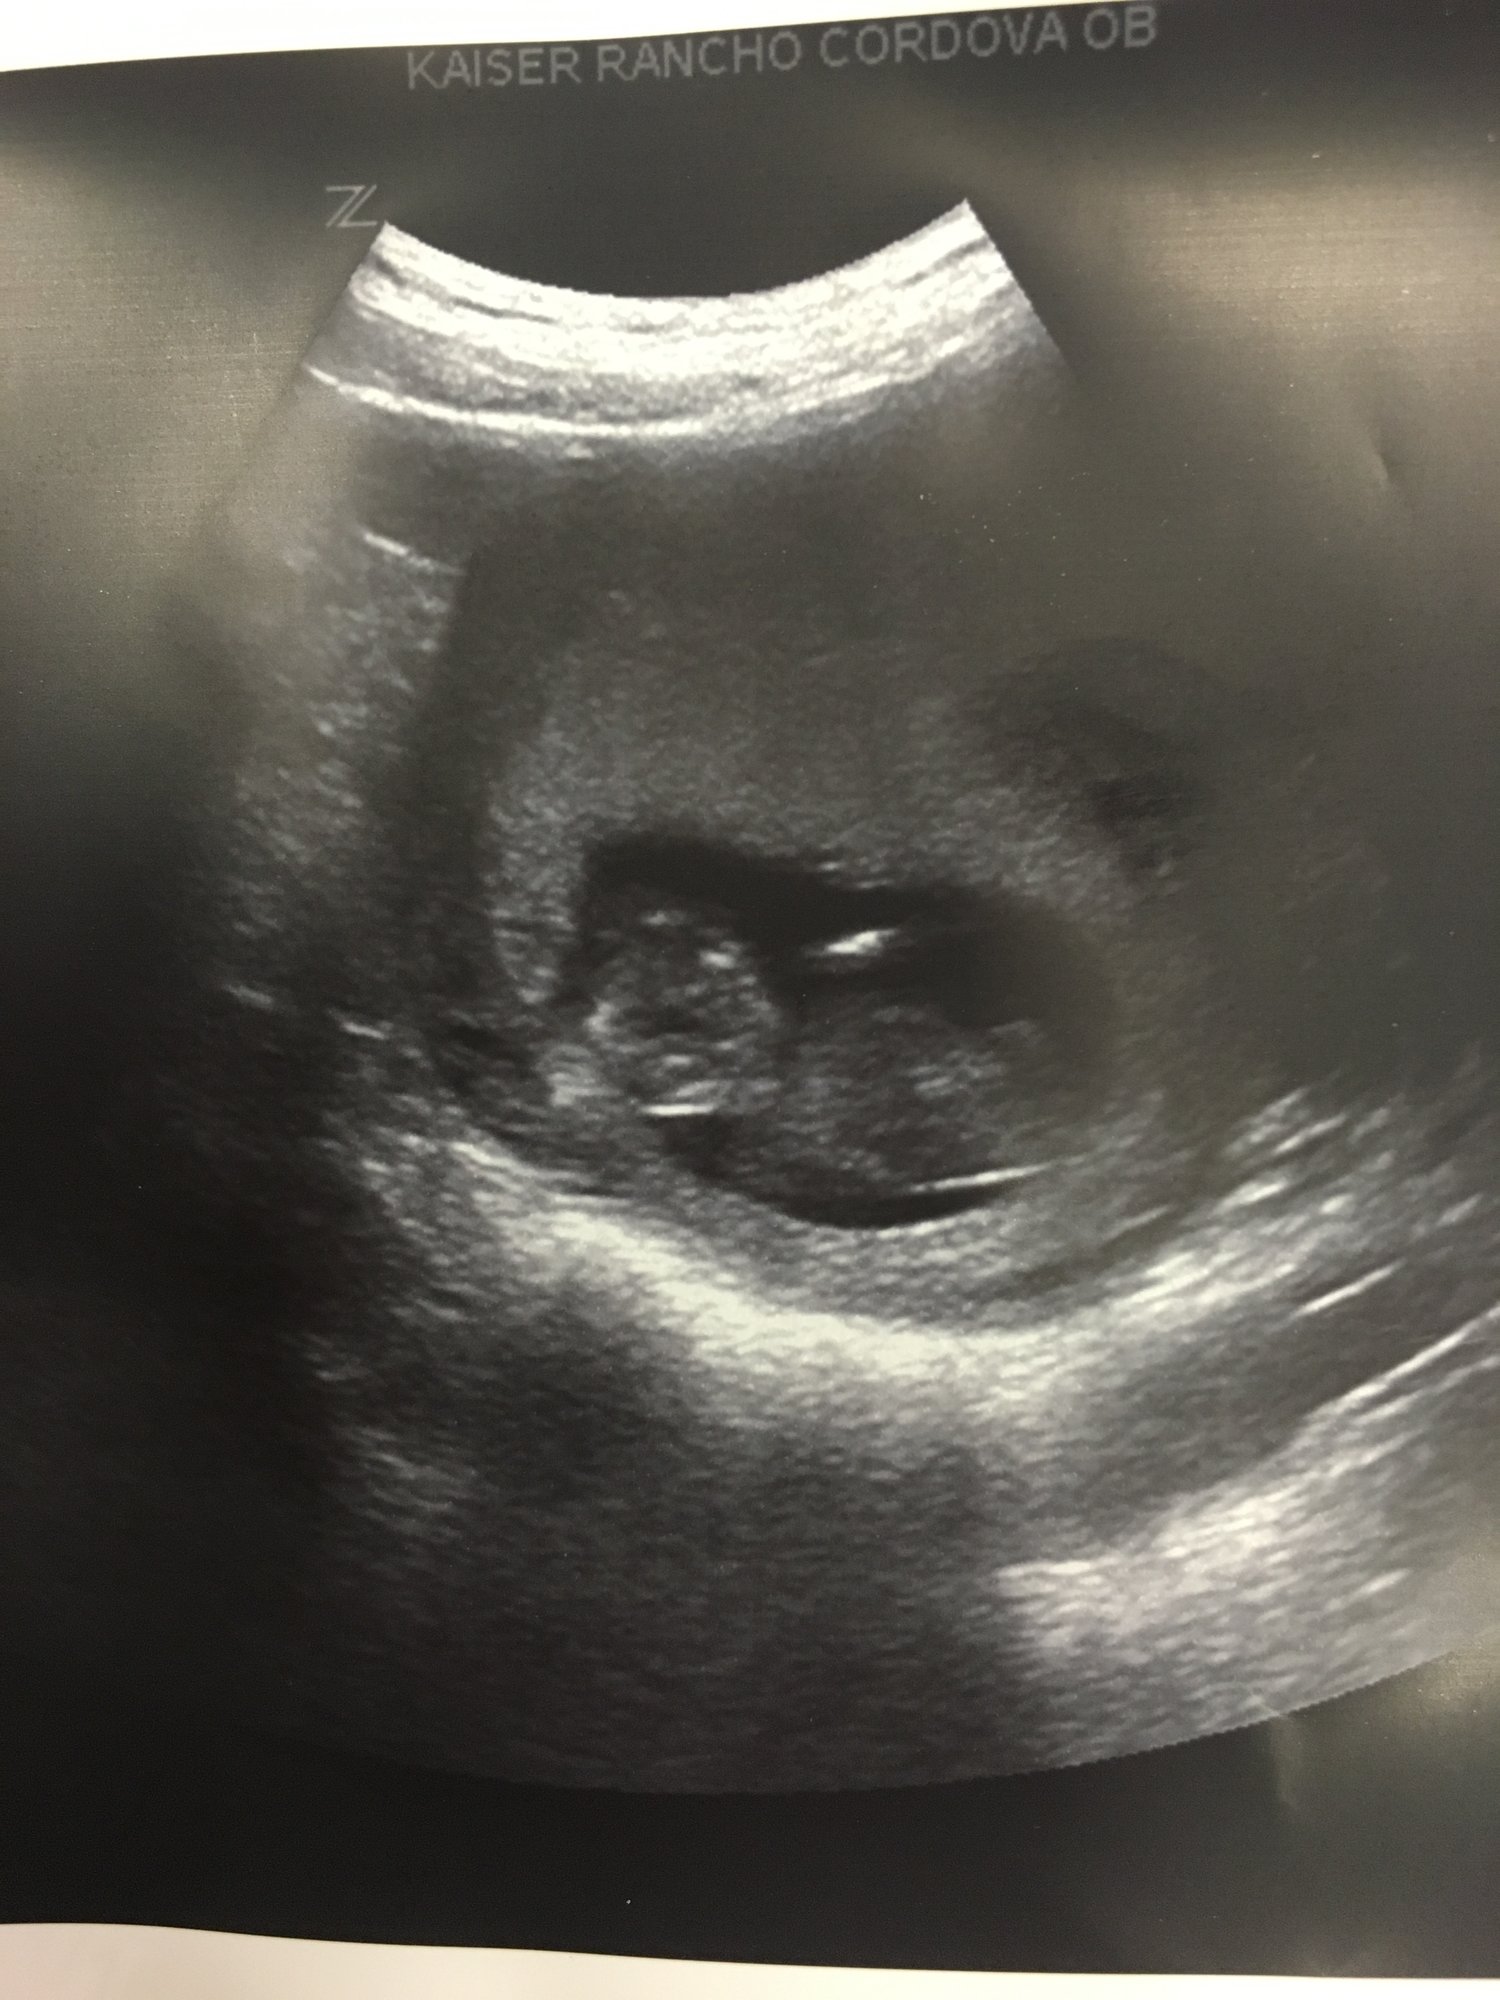

12w on the dot HR 167. Little stinker wouldn't sit still so the U/S took over an hour for the NT, and they ended up going from the external to internal U/S. Hey, you won't see me complaining that I got to watch the baby wiggle around for over an hour! Sorry the pics are so huge- I snapped a pic with my phone after cropping out my info